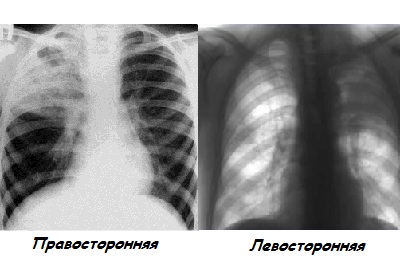

Рентгенодиагностика бронхопневмонии: Советы и примеры

Раздел: Альбом открытий